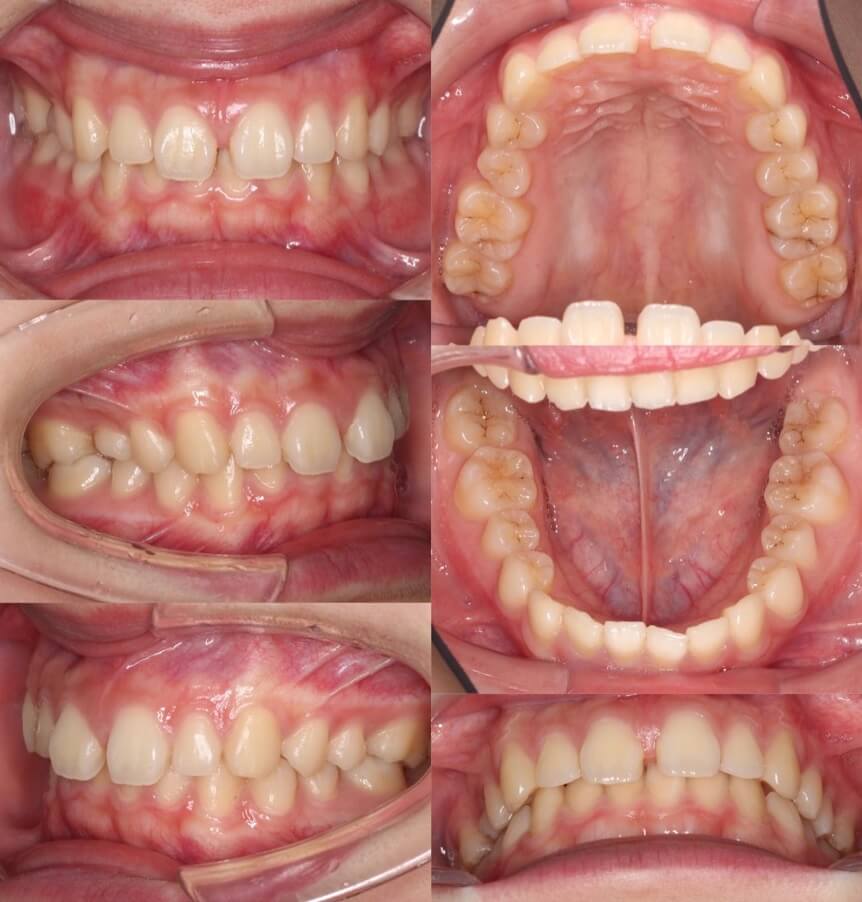

高校生女性・マウスピース型矯正

隙間が前歯の正中部にしかない比較的容易なケースです。過蓋咬合も併発していたため、上下の歯列をマウスピースで動かしました。このようなすきっ歯のケースは部分矯正治療を希望される患者さんも多いのですが、過蓋咬合(前歯の深い噛み合わせ)もある場合は全体矯正治療の適応になります。

<症例概要> 難易度★☆☆☆☆

主訴:すきっ歯

年齢・性別:10代女性

症状:正中離開・過蓋咬合

治療方針:空隙閉鎖+右上歯列後方移動

治療装置:マウスピース型矯正装置(アライナー装置)

固定装置:II級顎間ゴム

治療期間:1年7か月

アライナー枚数:24+33ステージ (7〜10日交換)

リテーナー:上フィックスタイプ+上下クリアタイプ

治療費用:990,000(税込)

前歯の空隙を閉鎖しながら、上方に持ち上げています。これにより過蓋咬合も改善します。